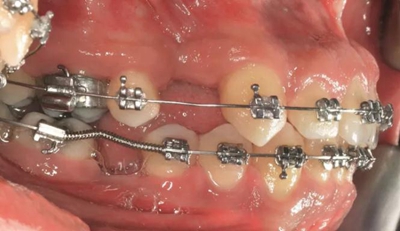

經(jīng)過最初1年的正畸排齊后,右側(cè)下頜第一磨牙無牙區(qū)的近遠中距離由6mm增至7mm,左側(cè)下頜第一磨牙的近遠中距離由7mm增至8mm(圖4)。取得患者知情同意后,采用與病例1中描述的相同技術(shù)和材料進行同期牙槽嵴增量和加速磨牙直立程序(圖5a-5g)。除了右側(cè)磨牙后區(qū),在右側(cè)第二和第三磨牙根部之間也進行了去皮質(zhì)術(shù)(圖5d)。骨增量術(shù)后,即刻將0.016×0.022 英寸帶有30° 后傾彎的鈦鉬合金絲(Dentsply)置于兩側(cè)。6周后,以半個托槽的距離進行主弓絲套推簧雙側(cè)輕加力(圖5h)。

圖5h. 通過帶有一個后傾彎的鋼絲以及開放彈簧的半托槽距離輕加力實現(xiàn)了生物力學直立磨牙

術(shù)后3個月,右側(cè)第一磨牙的空間約為9mm(3個月中增加了1.6mm),逐漸接近了對側(cè)第一磨牙的空間(也約9mm)(圖6a)。術(shù)后7個月的錐束CT顯示,右側(cè)第一磨牙區(qū)域獲得了2.5mm的水平骨增量(圖6b 和c)。左側(cè)第一磨牙的無牙區(qū)保持相同的尺寸,在種植體植入前也需要骨增量。